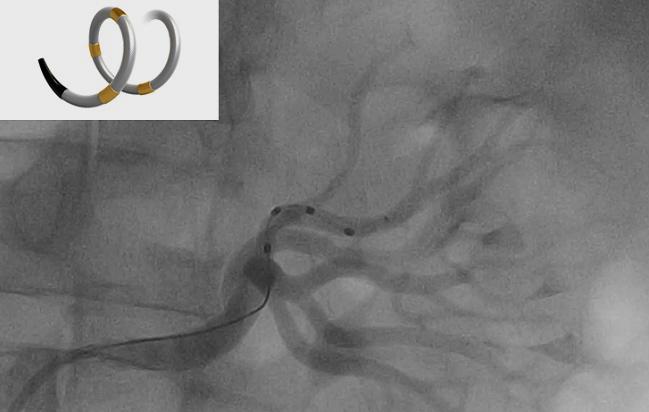

Her expertise in renal denervation will no doubt prove useful given Medtronic’s other announcement Monday: that it has received approval from the US Food and Drug Administration to begin an investigational device exemption trial to evaluate the Symplicity Spyral system, which is already approved for use in more than 50 countries around the world but remains investigational in the United States and Japan.

The SPYRAL HTN Pivotal Trial will include up to 433 patients with untreated hypertension—not taking antihypertensive medications—at 50 sites in the United States, Europe, Australia, and Japan and randomize them to renal denervation or a sham procedure. The primary efficacy and safety endpoints are 24-hour blood pressure at 3 months and the incidence of major adverse events through 1 month.

The news comes after the positive results of the SPYRAL HTN-OFF MED study were released last year at the European Society of Cardiology Congress, showing that the updated catheter reduced blood pressure in patients with untreated mild-to-moderate hypertension compared with a sham procedure. The study, designed along with other pilot studies after efforts to figure out what went wrong in the failed SYMPLICITY HTN-3 trial, for which Mauri served on the steering committee, provided some hope that renal denervation could be revived.

Photo Credit: Adapted from: Michael Böhm. First Results From the SPYRAL Hypertension Program (OFF-MED Study). Presented at TCT 2017. Denver, CO.